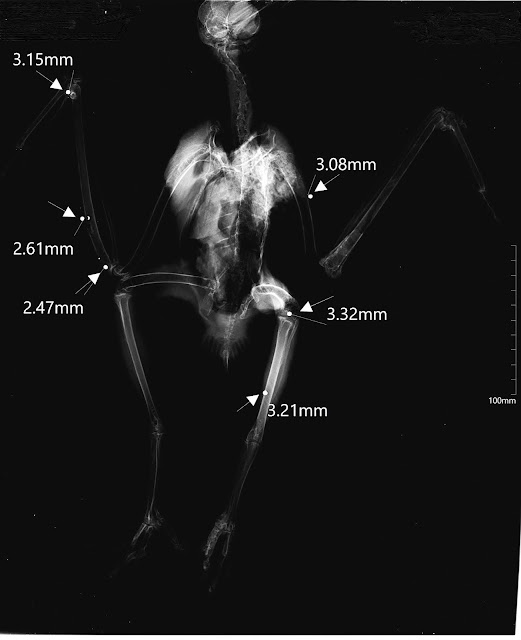

| Raio-X da águia-d’asa-redonda. |